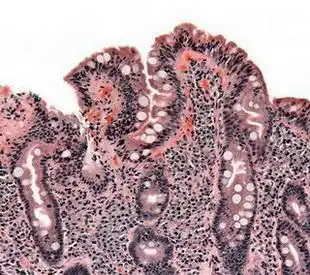

乳糜泻诊断